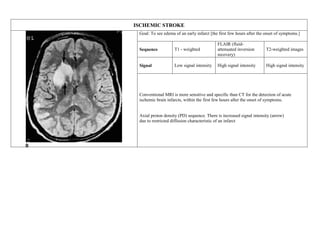

ISCHEMIC STROKE

Goal: To see edema of an early infarct [the first few hours after the onset of symptoms.]

Sequence T1 - weighted

FLAIR (fluid-

attenuated inversion

recovery)

T2-weighted images

Signal Low signal intensity High signal intensity High signal intensity

Conventional MRI is more sensitive and specific than CT for the detection of acute

ischemic brain infarcts, within the first few hours after the onset of symptoms.

Axial proton density (PD) sequence. There is increased signal intensity (arrow)

due to restricted diffusion characteristic of an infarct